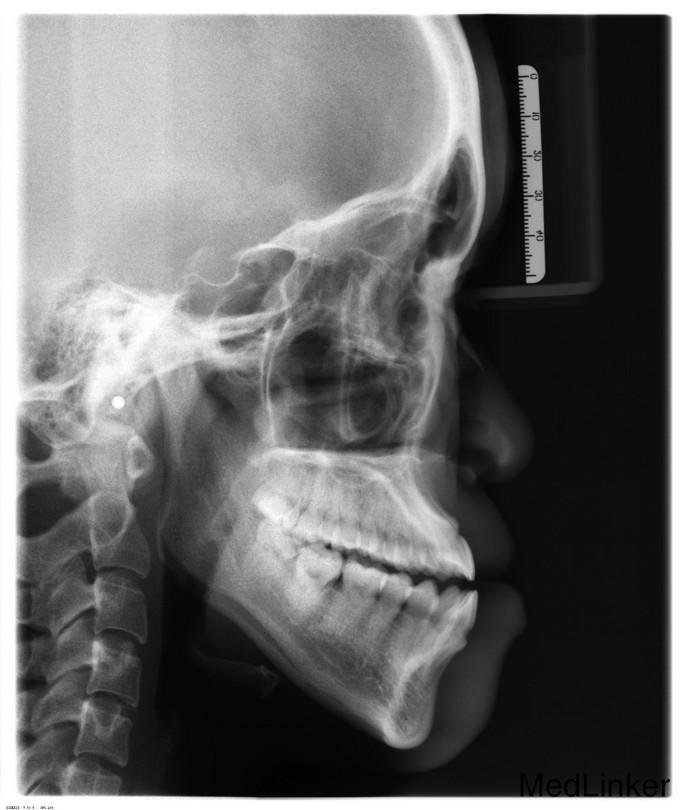

正颌术后半年余,患者2015年1月12日因“下颌偏斜10余年”来我院治疗,于2015年1月16日行“双侧下颌骨升支矢状劈开截骨前徙术+去骨皮质术+骨内坚固内固定术+上下颌牵引钉植入术”,今为取出下颌骨存留钛板来我院就诊,门诊以"正颌术后钛板存留"收入

双侧颜面部基本对称,下颌稍左偏,侧面观下颌稍突,双侧颞下颌关节区无弹响、压痛,双侧髁突活动度正常。开口度3.5cm,开口型“↘”。口内检查:全口恒牙列,口腔卫生一般,上下牙列中线不对齐,下牙列稍左偏,前牙对刃合。